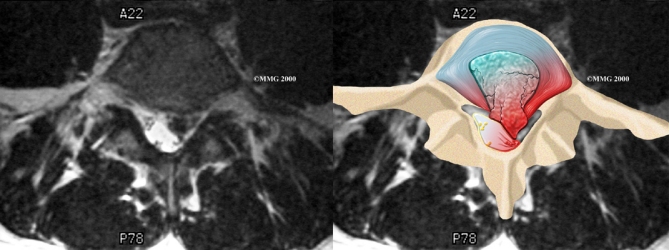

Herniation occurs when the nucleus in the center of the disc pushes out of its normal space. The nucleus presses against the annulus, causing the disc to bulge outward. Sometimes the nucleus herniates completely through the annulus and squeezes out of the disc.

Although daily activities may cause the nucleus to press against the annulus, the body is normally able to withstand this pressure. However, as the annulus ages, it tends to crack and tear. It is repaired with scar tissue. This process is known as degeneration. Over time, the annulus weakens, and the nucleus may begin to herniate (squeeze) through the damaged annulus. At first, the pressure bulges the annulus outward. Eventually, the nucleus may herniate completely through the outer ring of the disc.

Herniation causes pain from a variety of sources. It can cause mechanical pain. This is pain that comes from the parts of the spine that move during activity, such as the discs and ligaments. Pain from inflammation occurs when the nucleus squeezes through the annulus. The nucleus normally does not come in contact with the body's blood supply. However, a tear in the annulus puts the nucleus at risk for contacting this blood supply. When the nucleus herniates into the torn annulus, the nucleus and blood supply meet, causing a reaction of the chemicals inside the nucleus. This produces inflammation and pain. A disc herniation may also put pressure against a spinal nerve. Pressure on an irritated or damaged nerve can produce pain that radiates along the nerve. This is called neurogenic pain.